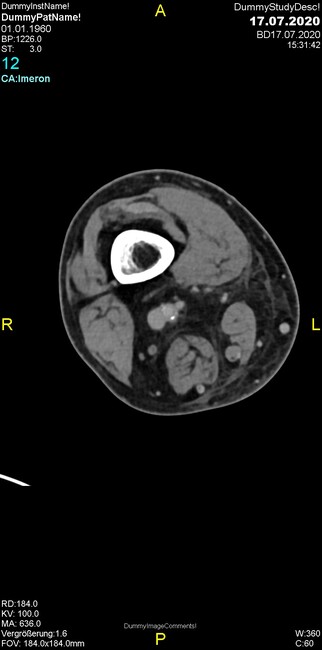

Um welche Modalitäten handelt es sich?

- Röntgen p.a. und lateral, CT coronar Knochenfenster, CT axial Weichgewebsfenster

- Röntgen p.a. und lateral, CT coronar Weichgewebsfenster, MR axial

Was fällt in der Projektionsradiographie auf?

- Verdichtung im Recessus suprapatellaris

- Aufhellungslinie in Projektion auf die Femurkondylen

- Erhöhter tibialer Slope

- Hypertransparenz tibial

- Subluxationsstellung im Kniegelenk

Was trifft auf den Befund zu?

- Der Befund beschränkt sich auf den Knochen.

- Es besteht hochakuter Handlungsbedarf.

- Der Befund ist tendenziell benigne.

- Der Befund ist tendenziell maligne.

- Der Befund weist einen Zusammenhang zum Patientenalter auf.

Was fällt in der CT im Knochenfenster auf?

- Mediale Gelenkspaltverschmälerung

- Dezente Erosion der fibulären Kortikalis

- Frakturspalt der lateralen Tibiametaphyse

- Weichgewebskalzifikationen lateral angrenzend an den Gelenkspalt

- Osteolyse der Tibiametaphyse unter Beteiligung der Kortikalis

Was kommt differentialdiagnostisch in Frage?

- Kompartmentsyndrom

- Osteomyelitis mit Weichgewebsanteil

- Metastase mit pathologischer Fraktur

- Rheumatoide Athritis

- Posttraumatische Verletzung